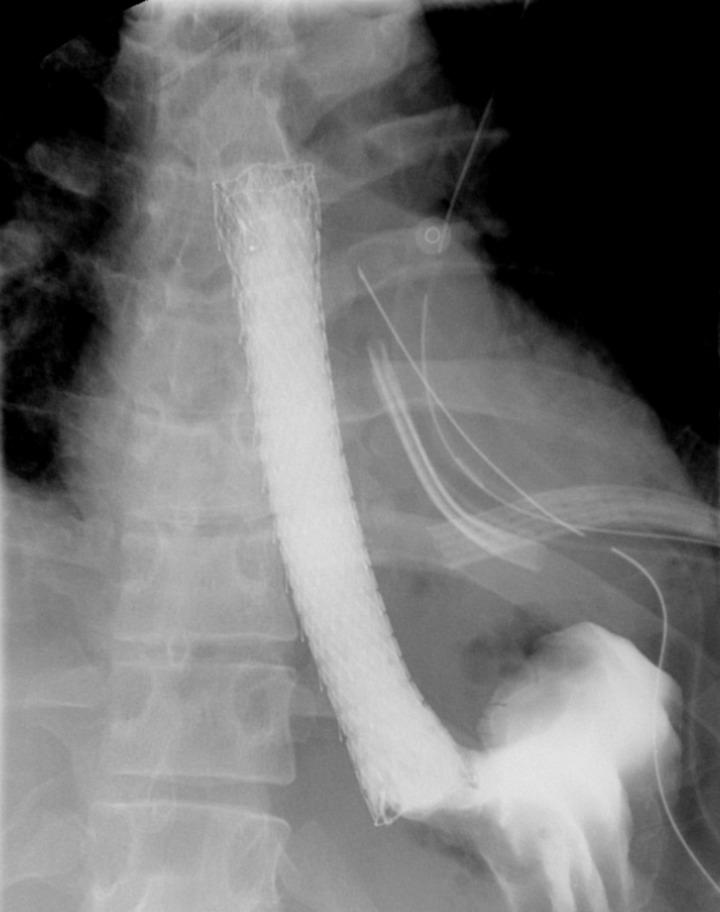

Eosinophilic esophagitis (EoE) is a rare disease of the esophagus that is characterized by eosinophilic infiltrate within the esophageal mucosa resulting in chronic inflammation and stenosis. It typically presents with symptoms of esophageal dysfunction with dysphagia and food impaction being the most common presenting complaints. Herein we describe a rare case presentation of a young patient with spontaneous esophageal perforation in the setting of undiagnosed EoE. We suggest that the placement of a covered esophageal stent can provide full closure of the perforation and restoration of the integrity of the GI tract without the need for more invasive open repair. The patient had a short recovery time with no reported postoperative complications upon 30 months follow up. We believe that it's important to consider and rule out EoE in patients with a history of dysphagia and esophageal perforation.

嗜酸性粒细胞性食管炎(EoE)是一种罕见的食管疾病,其特征是食管黏膜内嗜酸性粒细胞浸润,导致慢性炎症和狭窄。它通常表现为食管功能障碍的症状,吞咽困难和食物嵌塞是最常见的主诉。在此,我们描述了一例年轻患者在未诊断出EoE的情况下发生自发性食管穿孔的罕见病例。我们认为,放置带膜食管支架可以完全封闭穿孔并恢复胃肠道的完整性,而无需进行更具侵入性的开放修复。该患者恢复时间短,在30个月的随访中未报告术后并发症。我们认为,对于有吞咽困难和食管穿孔病史的患者,考虑并排除EoE很重要。